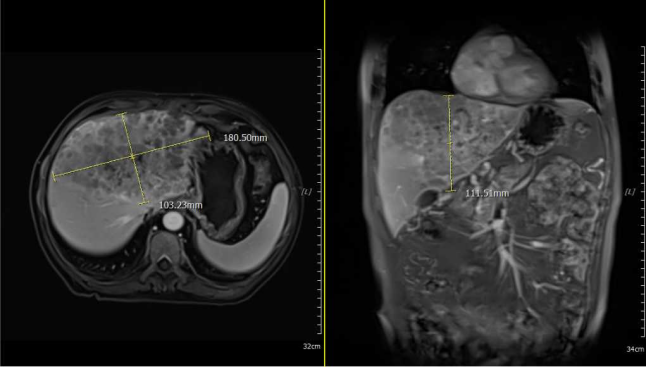

Baseline imaging at initial diagnosis

December 16, 2020, marked a hectic and critical day for Mr. Du. Burdened by year-end workloads, he had been working late into the night for days, skipping regular meals, which exacerbated his worsening "chronic malnutrition." Recalling the incident, Mr. Du vividly described: "A sudden onset of abdominal pain forced me to pause work, but the pain intensified relentlessly, leaving me restless. When I tried to stand up for water, everything went dark, and I collapsed." He was rushed to a hospital in Beijing, where diagnostic imaging revealed 18-cm hepatic mass causing intraperitoneal hemorrhage.

Mr. Du, upon regaining consciousness post-surgery, was incredulous to learn that his recent months of abdominal distension were not merely "indigestion," but rather the result of rampant cancer cell proliferation in his liver. Examination revealed that half of Mr. Du's liver had been occupied by a tumor, diagnosed as giant hepatocellular carcinoma. Due to the tumor's size and involvement of critical blood vessels, surgical resection criteria were not met. Subsequent treatment will involve systemic antitumor chemotherapy or localized radiotherapy.